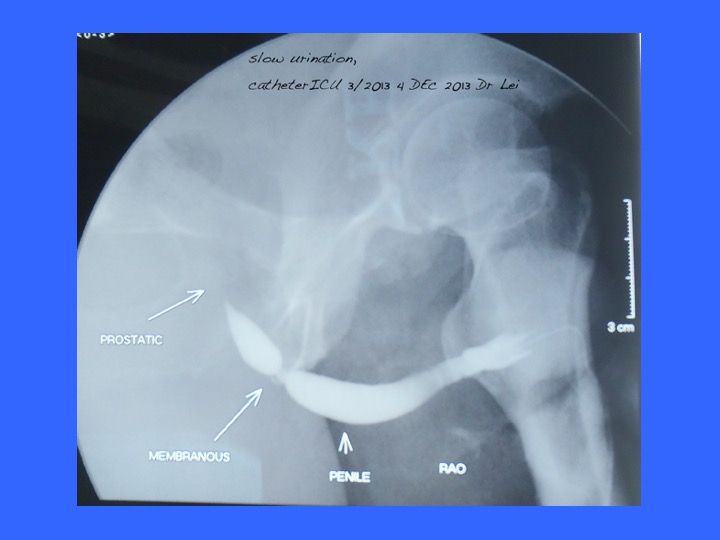

- Dr Clarence Lei Chang Moh, FRCS Urol (MMC No.: 024209, NSR 123533) Adjunct Professor, Universiti Malaysia Sarawak, Honorary Consultant SGH, Heart Centre Sarawak, Hospital KL; Consultant Urologist(Adult and Paediatric), Kidney, Urology, Stone, Prostate & Transplant) Normah Hospital, Petra Jaya, 93050 Kuching, MALAYSIA Tel: +6082-440055 e-mail: clarencelei@gmail.com telemedicine welcome; email or whatsapp+60128199880; standard charges RM235 for first & RM105 subsequent